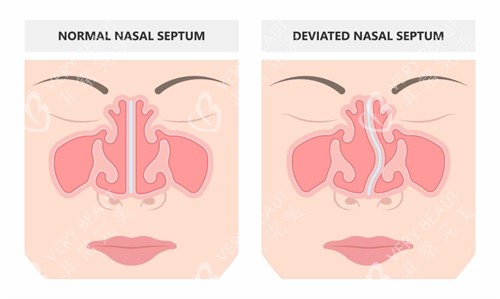

术前通过CT扫描重建鼻部三维模型,结合面部黄金比例和肌肉动态数据,定制“千人千面”方案。

区别于传统静态雕刻,动态建模可模拟微笑、皱眉等表情下的鼻部形态变化,避免术后表情僵硬。